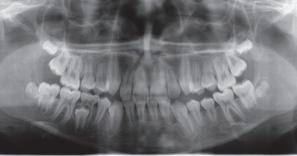

Blandt tandstillingsfejl anses transposition for det vanskeligste at korrigere. Accepteres transpositionen, vil en nivellering ofte føre til et resultat, der både funktionelt og æstetisk er utilfredsstillende. Ikke desto mindre er accept af en transposition den dominerende behandlingsstrategi, hvis man skal dømme efter kasuistikker i litteraturen.

Formålet med denne artikel var at præsentere en litteraturoversigt over forekomsten og ætiologien samt diskutere de »cost-benefit«-overvejelser, som har haft indflydelse på behandlingsstrategien og på beslutningen om at acceptere eller korrigere. Et andet formål var at diskutere behandlingen af 12

patienter med transpositioner; otte mellem hjørnetænder og 1. præmolar og fire mellem hjørnetænder og laterale fortænder. Hos de ni patienter blev transpositionen korrigeret inden for normal behandlingstid. Dette kunne tilskrives, at behandlingen blev foretaget med et segmenteret apparatur, der tillod differentiering mellem aktive og passive enheder, og som var designet således, at det optimale kraftsystem blev påført de tænder, der skulle flyttes. To patienter blev behandlet med ekstraktioner, en pga. parodontale problemer og en anden pga. trangstilling. Transpositionen blev accepteret hos en patient, fordi tandretningen var påbegyndt af anden tandlæge.

Ciarlantini R, Melsen B. Maxillary tooth transposition: Correct or accept? Am J Orthod Dentofacial Orthop 2007; 132: 385-94.